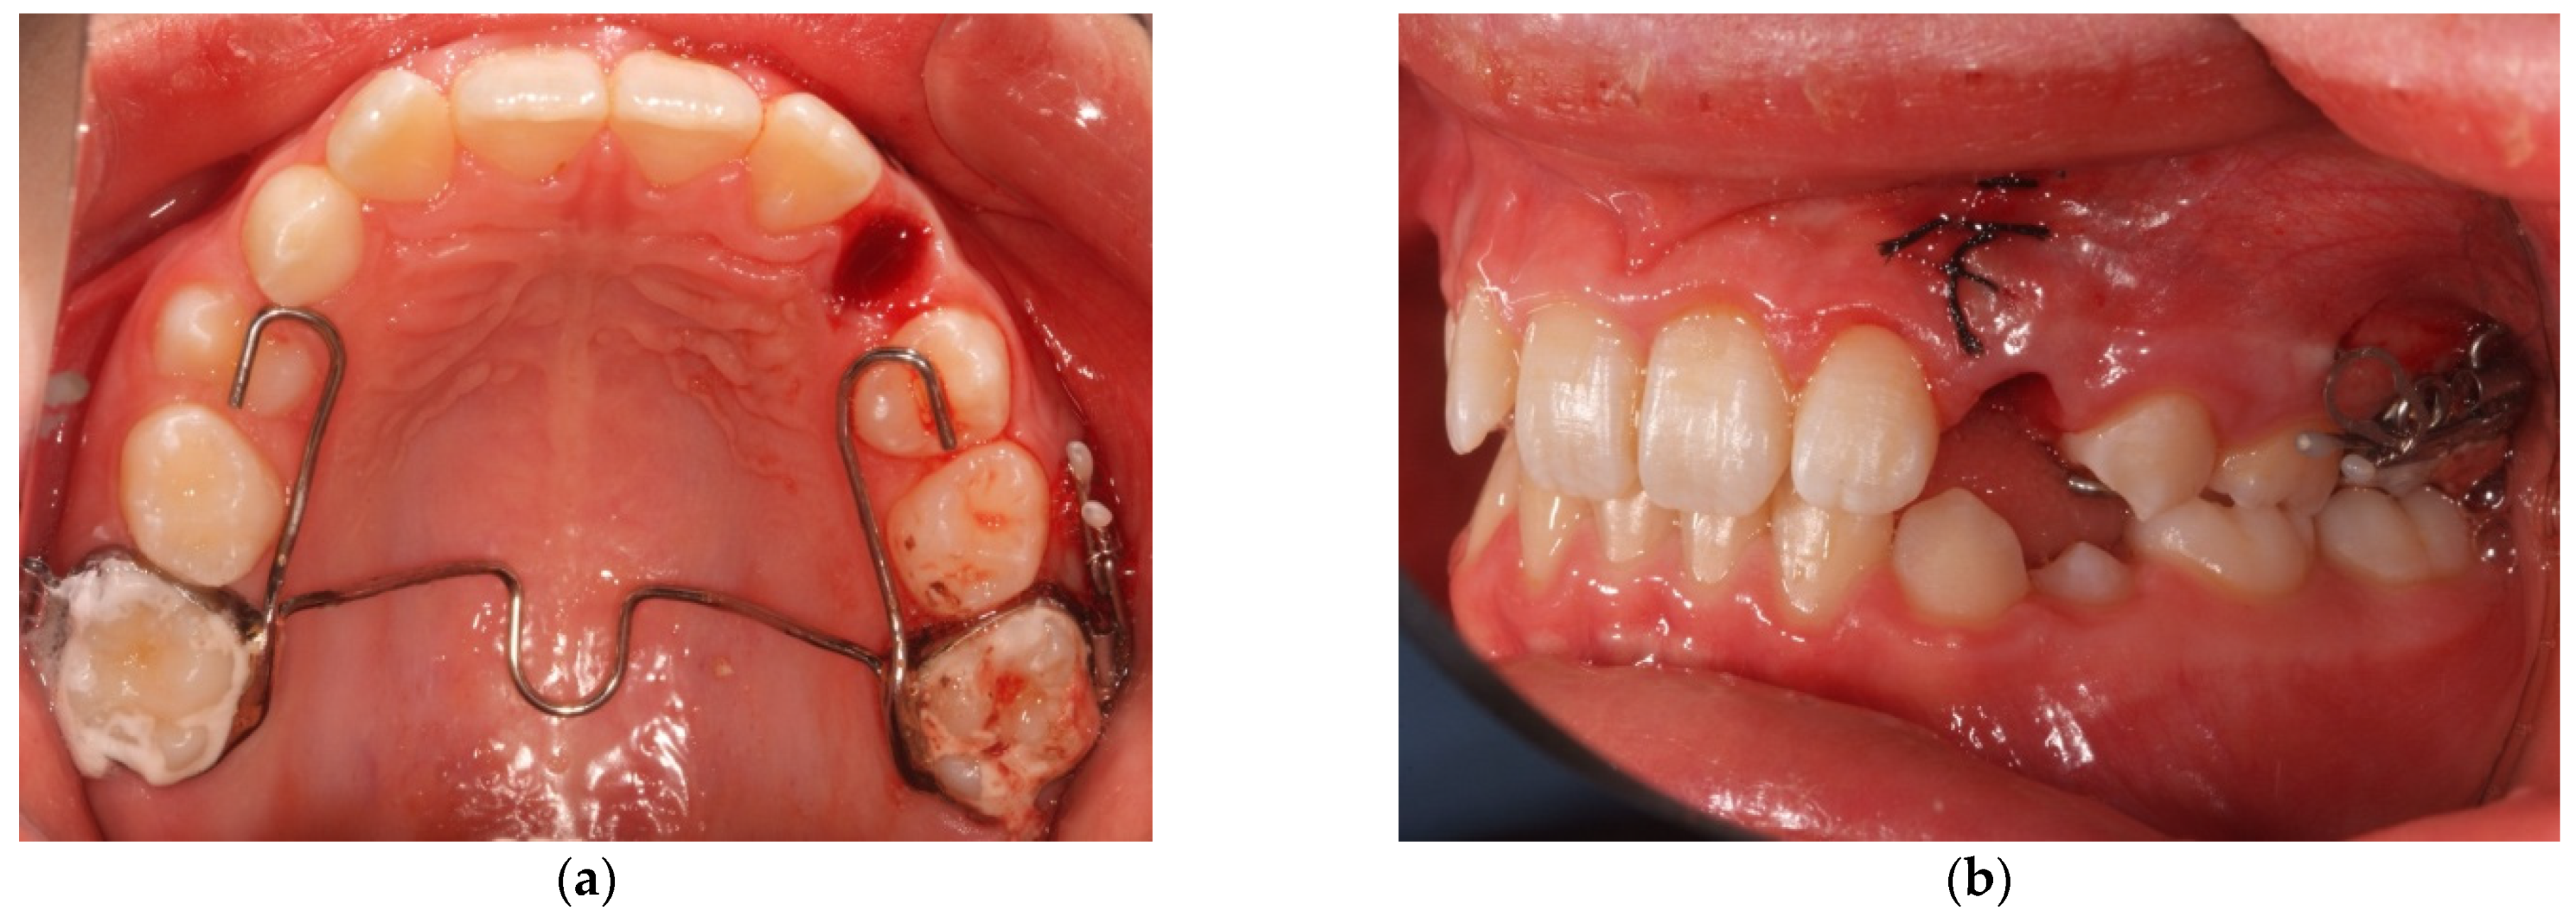

- A second vertical incision is made between the first and second premolar, and the sub-periosteal tunnel is created with a periosteal elevator to connect the two incisions from front to back (Figure 4);

- After a good hemostasis is reached, the button is attached to the buccal canine crown’s surface, following all necessary steps including enamel etching with 37% orthophosphoric acid for 30 s and applying adhesive. Therefore, the button is connected by means of a metal ligature to a 150 gr closed coil spring (NiTi). At the distal end of the NiTi coil, another metal ligature is inserted to facilitate the passage of the traction system under the subperiosteal tunnel (Figure 5);

- Then, the second metallic ligature is inserted in the subperiosteal tunnel to leak out from the posterior vertical incision. Alternatively, the Klemmer forceps can be inserted through the posterior vertical incision and pushed forward inside the tunnel until its end is visible from the anterior incision, to take the spring end and train it posteriorly until it exits from the rear end of the tunnel;

- After steps 1–5 for canine preparation, the previously prepared intraoral anchorage devices are banded to the first molars with glass–ionomeric cement

- Adequate/Inadequate Interadicular Space for The Insertion of The Miniscrew: The positioning of TADs requires a careful choice of the insertion site to select a position useful for the traction of the impacted teeth but respectful of the teeth and of other anatomical structures. The right selection of the patient performed through an accurate study of the radiographic images is essential, preferably on a 3D imaging of the interested arch. A correct inter-radicular space between the first molar and the second premolar is necessary and should be selected adding 1 mm of bone width and 0.5 mm of periodontium width on both sides to the screw diameter measurement. If any adequate inter-radicular space is available, as often occurs in the patient with a mixed dentition, the variant of the technique provides an anchorage to the distalizing force by an intraoral device, usually consisting of a palatal bar with rests on the premolars and a vertical vestibular arm to which the closed coil-spring should be fixed by a metal chain. A similar vestibular arm can in the same way be soldered also on palatal expanders devices eventually needed for the orthodontic therapy.